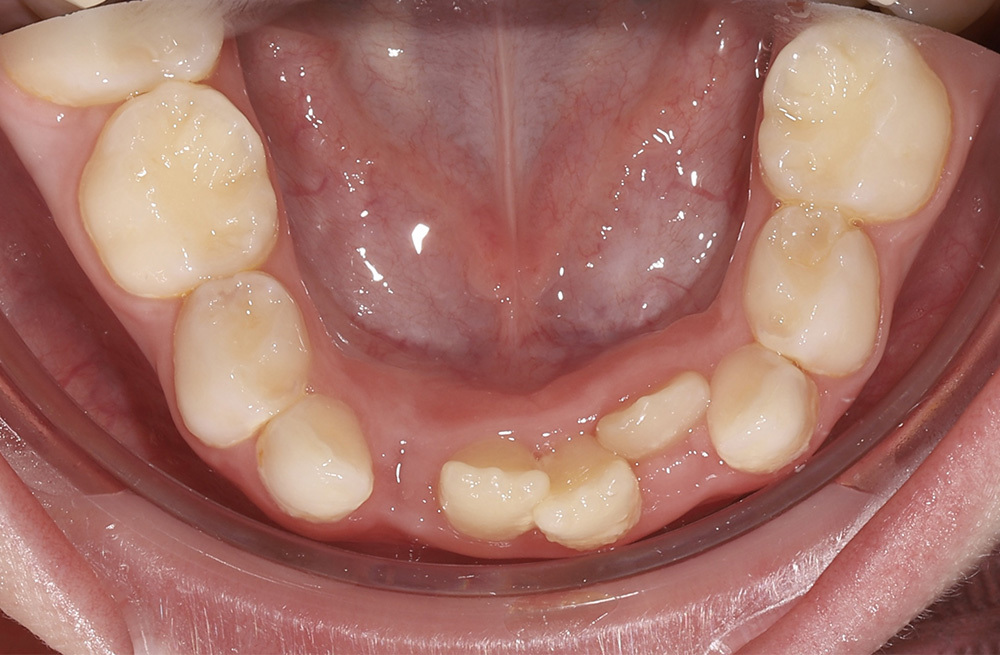

Два этапа ортодонтического лечения у семилетней пациенткиот сложного нарушения прикуса до коррекции положения языка